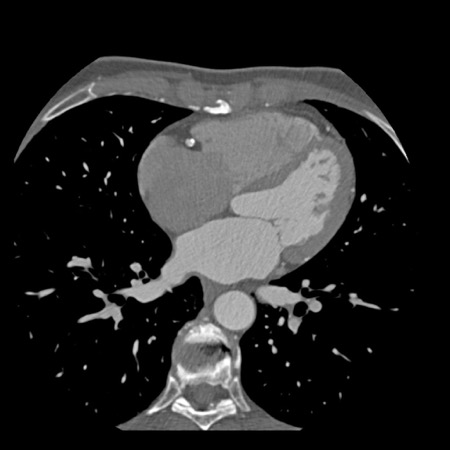

case 2 – CAD-RADS 5/P2/S

First, scroll through the CTA images.

How would you describe the findings on the coronary CTA?

The findings are:

- Stent in the mid

LAD with low-attenuation within the stent suggestive of minimal in-stent

restenosis (<25%). Non-calcified plaque distal to the stent

causing mild stenosis (25-49%). Notice bridging on a short segment in

the distal LAD. - Non-calcified

plaque in the LCX causing mild stenosis (25-49%). - Occlusion of the

proximal OM1 branch with distal filling. - Calcified and

non-calcified plaques in the proximal RCA causing mild (25-49%) stenosis. - Total plaque burden

is moderate based on SIS (four segments including proximal RCA, mid LAD, prox

LCX and OM1).

Due to the occlusion of OM1 branch and presence of the stent, this case

reads as CAD-RADS 5/P2/S, which means that this patient needs further

diagnostic workup.